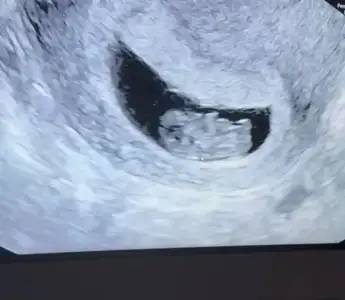

ben de araya kaynasam? daha önce buraya atmıştım ama hiç tahminde bulunan olmadı.ilki 6 hafta ikincisi 7+3.6-7 haftalık ultrason varmı yollar mısın Bi daha bakim merak ettim

doktor bir şey demedi ama.Vajinal ultrason ise erkek karın ultrasonu ise kızben de araya kaynasam? daha önce buraya atmıştım ama hiç tahminde bulunan olmadı.ilki 6 hafta ikincisi 7+3.

Kıza benziyor

Bana da yorum yapar mısınKıza benziyor